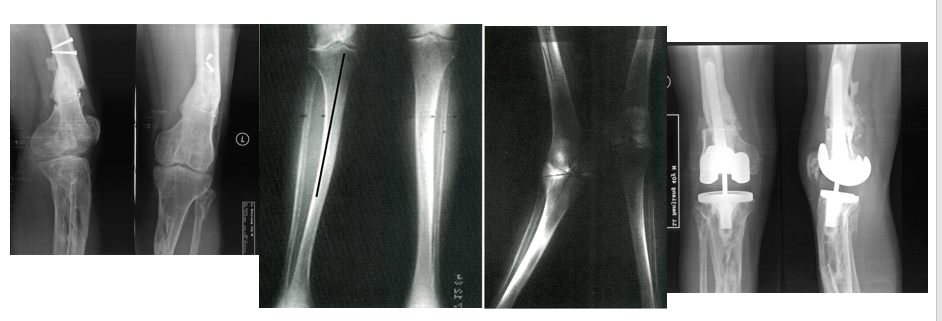

人工膝关节置换术(Knee replacement surgery)是骨科目前最常用且疗效确切的技术之一。TKA手术可以说是一个毫米级的手术,要想达到患者术后满意,精确的手术技巧是保证成功的必要条件。

关键一、切骨与对线:正确判断定位系统

正确的下肢力线

正确的关节线和胫骨切骨量